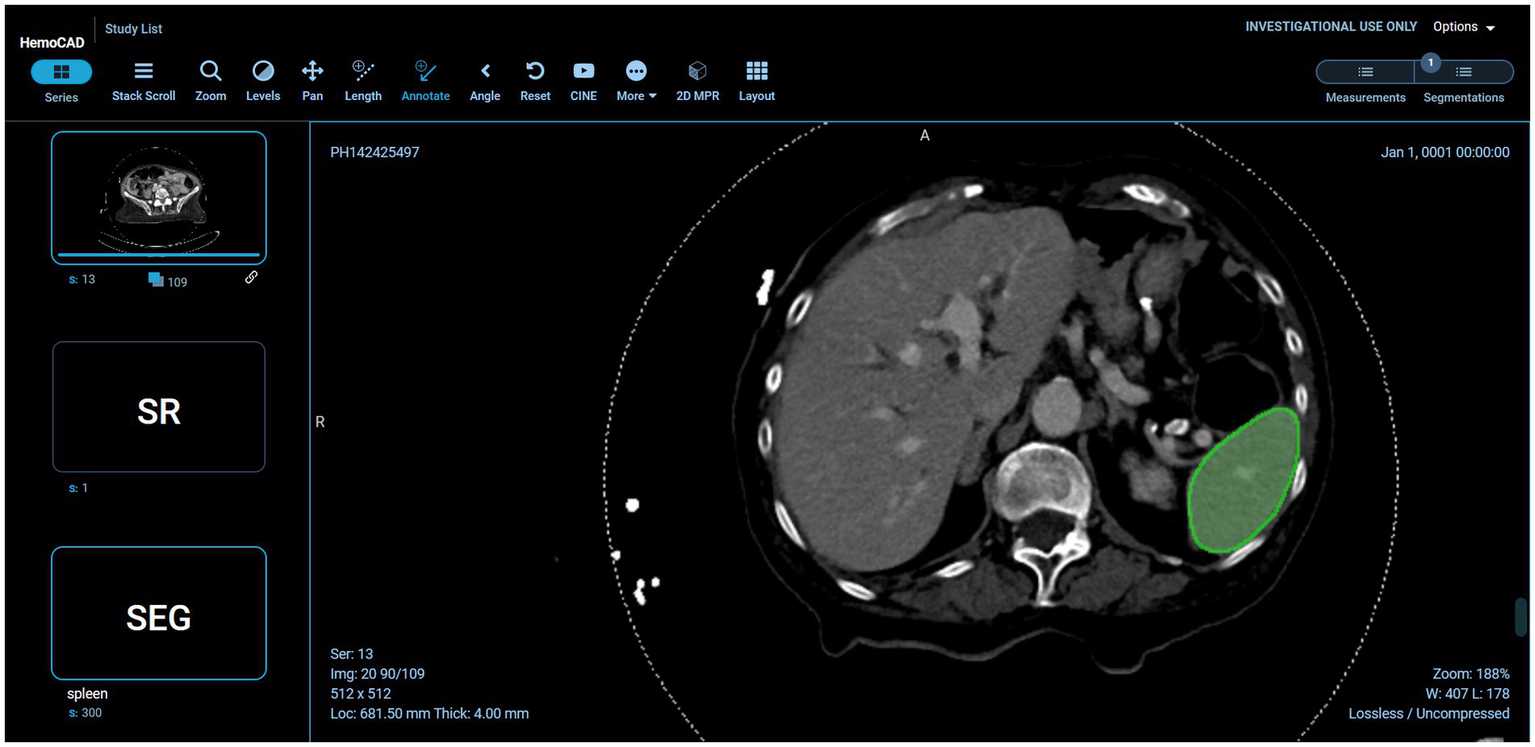

Example visual results using the OHIF viewer (35) with the DICOM SEG mask overlaid on the linked anonymized DICOM series are shown (for pelvic hematoma segmentation, see Figure 3; for splenic segmentation, see Figure 4). A modular structured report element with a statement of “Splenic volume: 40 mL” is shown in Figure 5.

Figure 4

Interoperability using various models on the back-end. In this case, the pelvic hematoma model was swapped out for a public model trained on the spleen segmentation dataset (task_009 spleen) from the public nnU-net repository (https://zenodo.org/record/3734294).